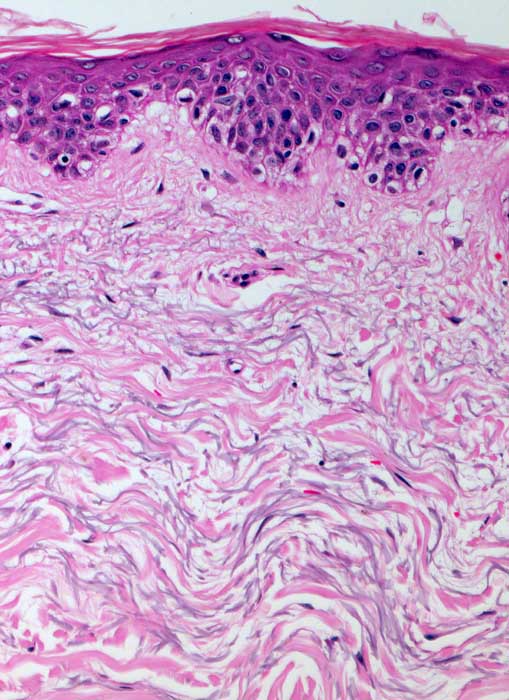

PathoPic ID 6613 - solare Elastose

solare Elastose

Haut, obere Extremität

Haut

Zahlreiche grau gefärbte Fasern in der Dermis sprechen für eine deutliche aktinische Schädigung der Haut.

Malignes Melanom am Vorderarm. Bild zeigt Haut aus der Umgebung des Melanoms.

Melanom am Vorderarm.

Histologie

200

60